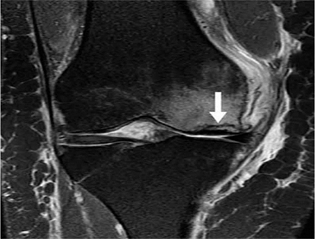

Hình 6. Nốt sần sụn chêm. Hình ảnh pd sagittal cho thấy một nốt sần hình sụn (mũi tên) ở vùng của rễ sụn trung gian sừng sau.

Hình 7. Vết rách ngang sụn. Hình ảnh pd coronal xóa mỡ với tín hiệu tuyến tính trong sụn (mũi tên đóng) kéo dài đến mặt dưới của thân sụn bên, phù hợp với vết rách. Tín hiệu cao (mũi tên mở) ở mặt ngoài, mặt sụn giữa không kéo dài đến bề mặt tạo hình sụn và phù hợp với thoái hóa niêm mạc.